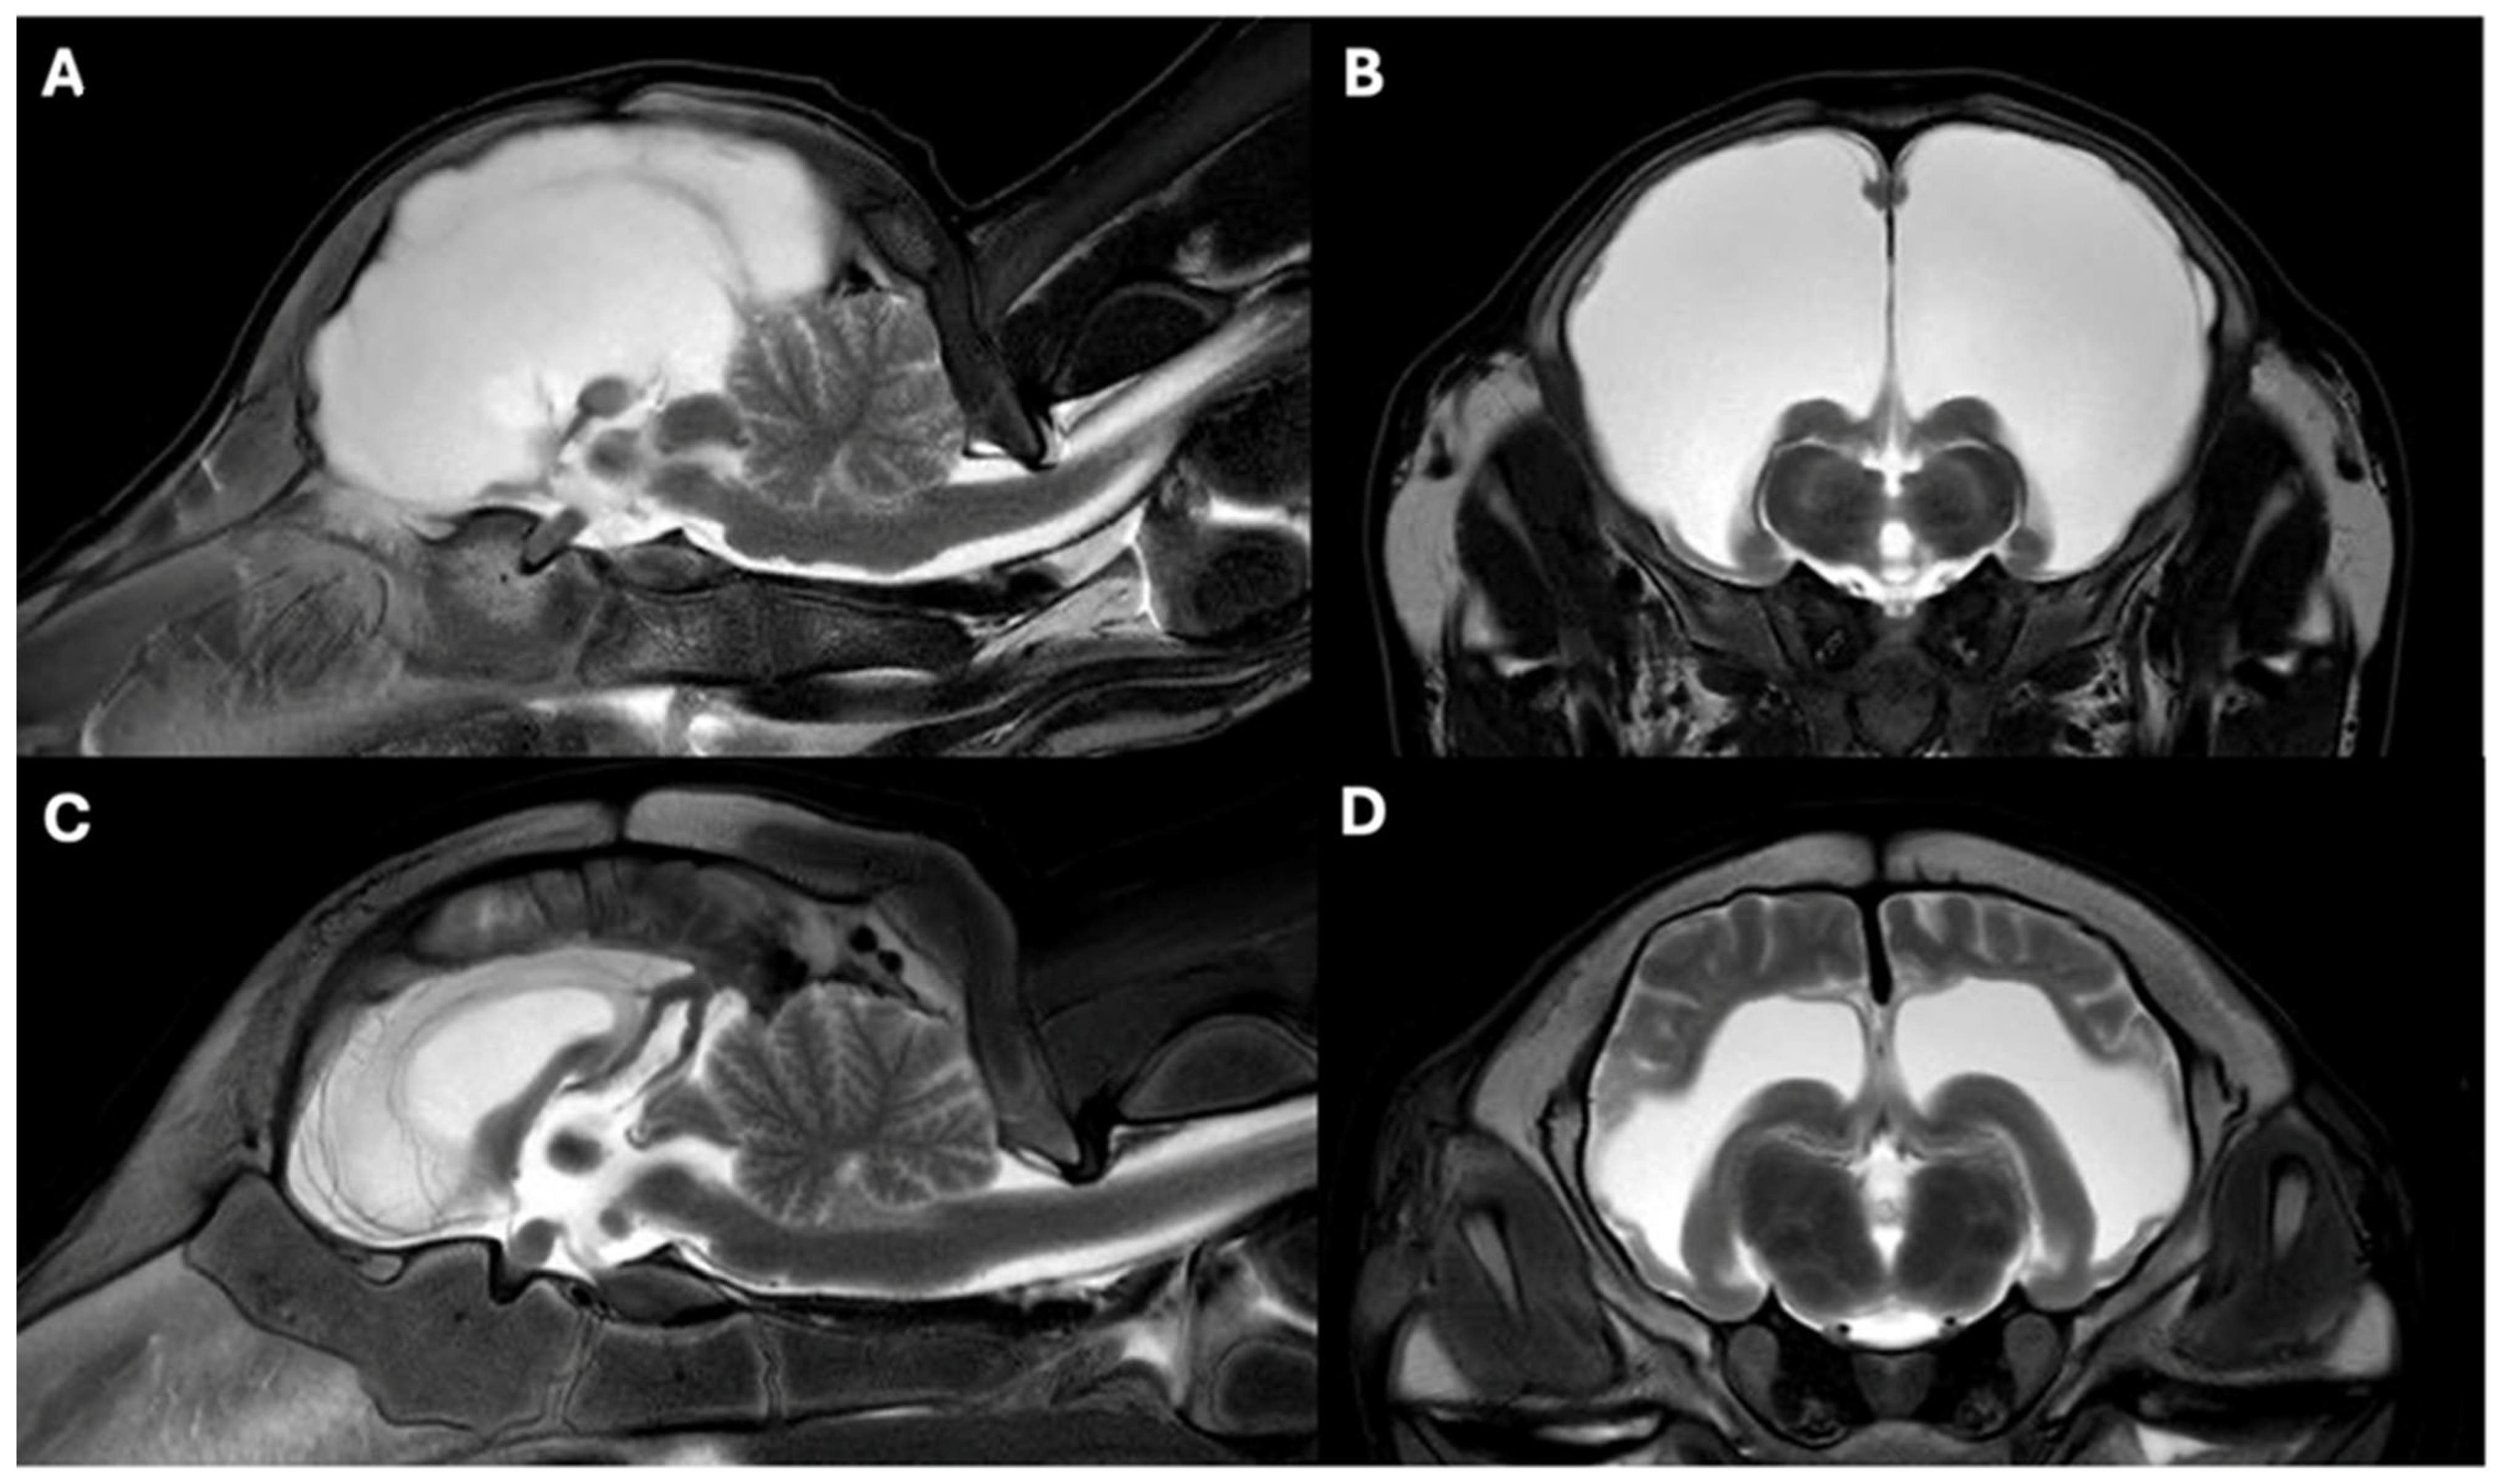

3.3. MRI Findings